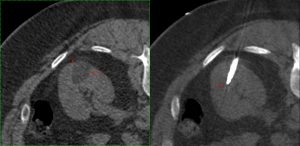

Cryoablation is ideal for renal tumors, mainly because the iceball (Fig. 2) and hence the ablation zone can be much better defined than other thermal ablative techniques such as RFA or microwave. The procedure is usually quite simple and straightforward, done without sedation, unless the patient is uncomfortable, in which case, conscious sedation is used.